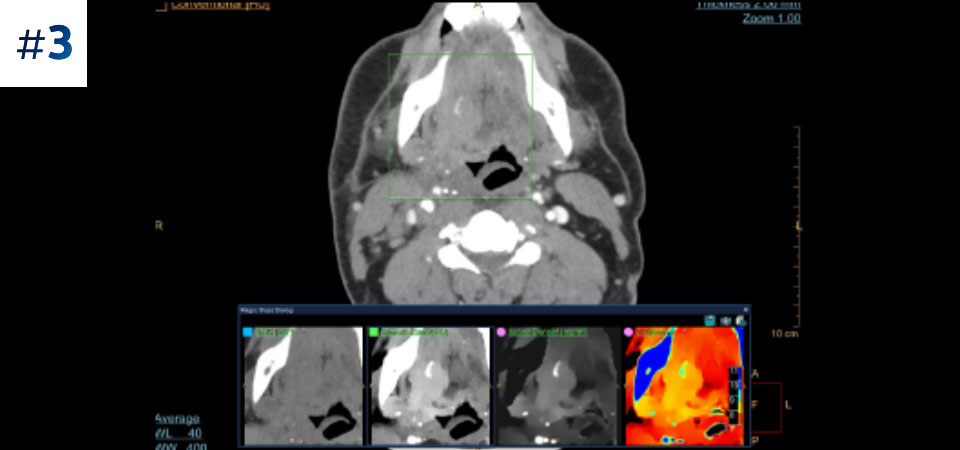

Guz szyi

Pobierz opisy przypadków tutaj

Sprawdź swoje odpowiedzi tutaj.

Zobacz różnicę pomiędzy tomografią komputerową opartą na detektorze spektralnym a konwencjonalną tomografią komputerową

Zobacz jak tomograf spektralny pomaga w diagnostyce pacjentów onkologicznych.